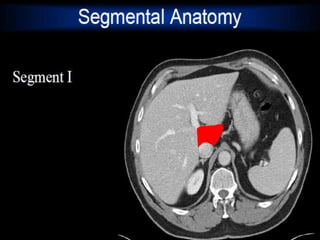

MRI anatomy images of the abdomen.

MRI anatomy imagesof the abdomen.